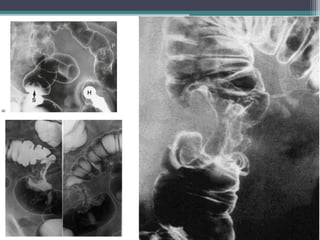

үзлэг • Багажийн шинжилгээ Ирригоскопи,ирригографи: ▫ Барийн сульфат. 4 шинж: • Нэмэлт сүүдэр • Хавдартай хэсэгт салст бүрхэвчийн зураглал алдагдах • Гэдэсний хөндий нарийсч хэлбэрээ алдах • Хавдартай хэсэгт гэдэсний гүрвэлзэх хөдөлгөөн алдагдах

41.